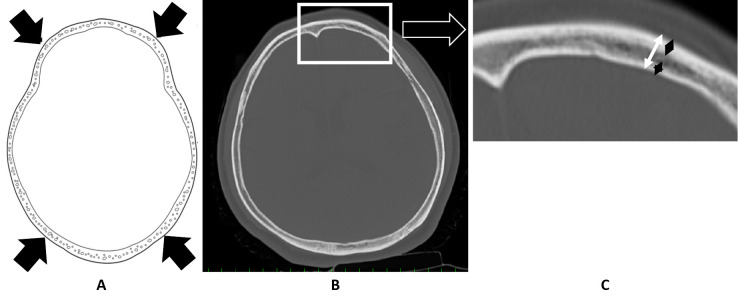

Introduction: A halo vest is an immobilization device widely used to stabilize the cervical spine. Pain and infection at the skull pin insertion site are common complications, but skull perforation is rare, and most published studies are case reports. This study aimed to identify risk factors for skull perforation by comparing patients who did and did not develop perforation.

Methods: Overall thickness and the thicknesses of the internal and external laminae of the skull at the skull pin insertion sites were measured on cranial computed tomography scans of 66 patients fitted with a halo vest. The results were compared between patients who did and did not develop perforation.

Results: Four patients developed perforations. All patients with perforation were older women, and their external and internal laminae were significantly thinner than those of patients who did not develop perforation.

Conclusions: The reported causes of skull pin perforation include infection around the pin, osteoporosis, and an enlarged frontal sinus. However, most patients with perforation in the present study were older women, and the cause was the thinning of the external and external laminae.